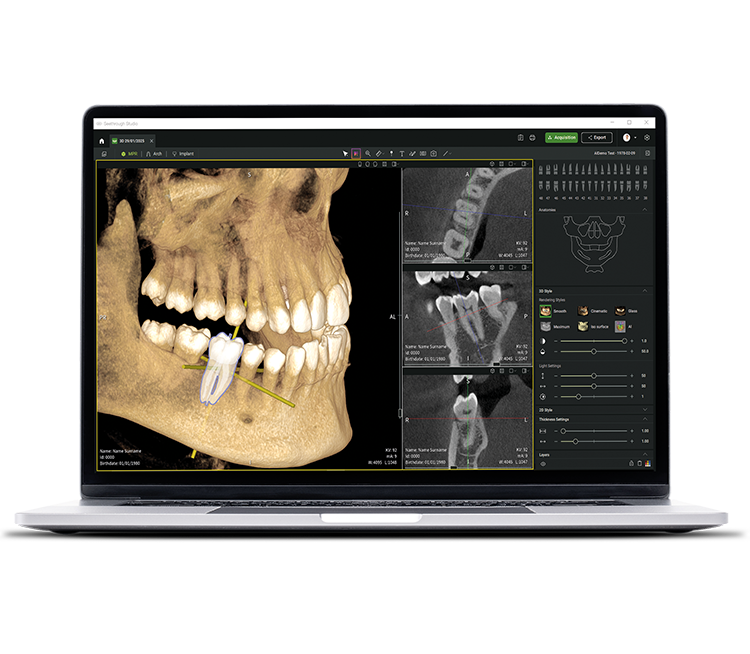

• Seethrough Studio

See tomorrow. See a new level.

Además de las sofisticadas tecnologías de hardware, el revolucionario software Seethrough Studio es el factor decisivo para el alto nivel de toda la gama de productos radiológicos de W&H. Con funciones útiles y algoritmos avanzados, Seethrough Studio es una solución completa que lleva los flujos de trabajo digitales y de radiología en odontología a un nuevo nivel.

Integración inalámbrica

Seethrough Studio puede integrarse fácilmente en su sistema de gestión de pacientes. Puede iniciar el software directamente desde el PMS sin tener que volver a introducir los datos del paciente.

Selección de FOV libre en la imagen radiográfica

Para obtener las imágenes adecuadas con la primera toma, seleccione el campo de visión deseado en la vista previa de la radiografía y ajuste libremente el área correspondiente. De esta forma se garantiza un posicionamiento preciso del FOV y se evita la reexposición.

Corrección de posición y movimiento

El avanzado algoritmo de corrección del movimiento lleva la calidad de imagen a un nuevo nivel tanto en imágenes 3D como 2D. Las imágenes 2D mejoran notablemente gracias a un sistema de enfoque automático de 21 capas integrado a la perfección con la corrección de posición.

Metal artefact removal (MAR)

Restaura la integridad de la imagen eliminando los artefactos metálicos y permite examinar imágenes con o sin MAR, para una visualización flexible y una mayor precisión diagnóstica.

Imágenes nítidas, detalladas y sin distorsiones

gracias a los avanzados algoritmos de Seethrough Studio.

Herramienta de planificación de implantes integrada

Además de la excelente calidad de imagen y el uso intuitivo, Seethrough Studio ofrece numerosas funciones útiles, como la herramienta de planificación de implantes integrada de serie para facilitar la visualización y la preparación del tratamiento.

Funciones asistidas por IA

Seethrough Studio utiliza varias herramientas de IA para obtener imágenes aún mejores, como la alineación de volúmenes 3D, la segmentación de dientes, la generación de líneas de arcos, el reconocimiento automático de nervios y una ayuda útil en la detección de patologías.